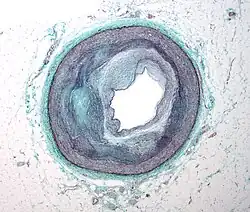

Although arteries are not typically studied microscopically, two plaque types can be distinguished:[72]

- The fibro-lipid (fibro-fatty) plaque is characterized by an accumulation of lipid-laden cells underneath the intima of the arteries, typically without narrowing the lumen due to compensatory expansion of the bounding muscular layer of the artery wall. Beneath the endothelium, there is a "fibrous cap" covering the atheromatous "core" of the plaque. The core consists of lipid-laden cells (macrophages and smooth muscle cells) with elevated tissue cholesterol and cholesterol ester content, fibrin, proteoglycans, collagen, elastin, and cellular debris. In advanced plaques, the central core of the plaque usually contains extracellular cholesterol deposits (released from dead cells), which form areas of cholesterol crystals with empty, needle-like clefts. At the periphery of the plaque are younger "foamy" cells and capillaries. These plaques usually produce the most damage to the individual when they rupture. Cholesterol crystals may also play a role.[73]

- The fibrous plaque is also localized under the intima, within the arterial wall, resulting in thickening and expansion of the wall and, sometimes, spotty localized narrowing of the lumen with some atrophy of the muscular layer. The fibrous plaque contains collagen fibers (eosinophilic), precipitates of calcium (hematoxylinophilic), and, rarely, lipid-laden cells.

However, atheromas within the vessel wall are soft and fragile with little elasticity. Arteries constantly expand and contract with each heartbeat, i.e., the pulse. In addition, the calcification deposits between the outer portion of the atheroma and the muscular wall, as they progress, lead to a loss of elasticity and stiffening of the artery as a whole.

The calcification deposits,[74] after they have become sufficiently advanced, are partially visible on coronary artery computed tomography or electron beam tomography (EBT) as rings of increased radiographic density, forming halos around the outer edges of the atheromatous plaques, within the artery wall. On CT, >130 units on the Hounsfield scale (some argue for 90 units) has been the radiographic density usually accepted as clearly representing tissue calcification within arteries. These deposits demonstrate unequivocal evidence of the disease, relatively advanced, even though the lumen of the artery is often still normal by angiography.